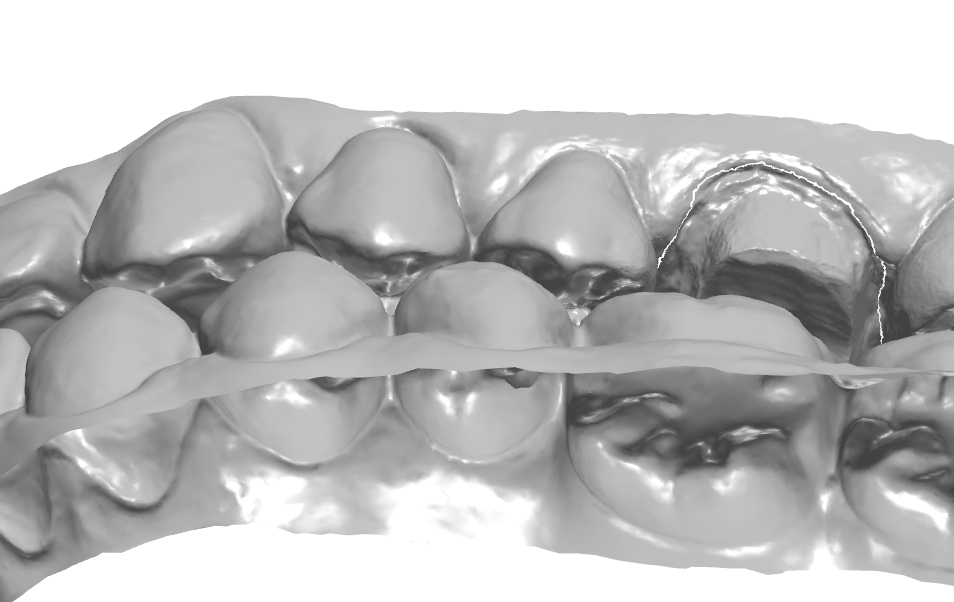

34번이나 35번을 생각보다 모양 잡기가 어려운것 같아 여러 방향에서의 모습을 찍어놓고

가끔식 보고자 하여 이렇게 기록으로 남겨본다.

협측에 있는 엠브레져 체크.

치경측에 존재하는 협측, 설측 엠브레져 체크.

치은 라인의 연속성 체크.

협측 풍융도 체크.

치은 라인가 치간 사이 엠브레져 체크.

보이는 방향에 따라 모양이 달라 보인다.

1치대2치 관계

치아의 수평피개 체크

각 치아의 풍융도 체크.